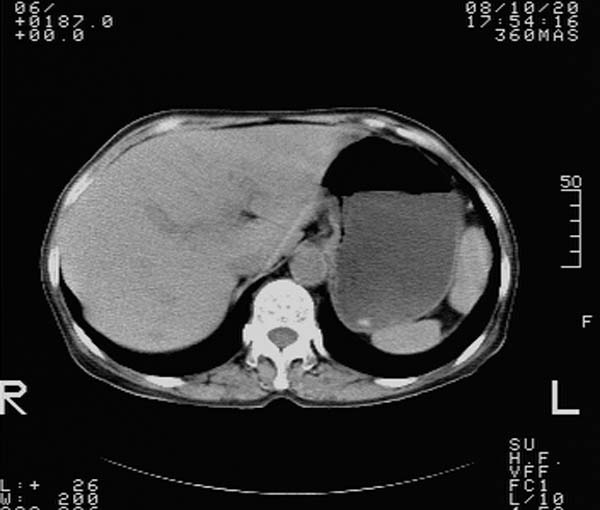

纵隔内及腹膜后广泛淋巴结肿大,脾大,肝内似可见低密度影,结合病史半年前发现颈小结节,逐渐增多增大,现双侧耳后、颌下及颈部表浅淋巴肿大。考虑淋巴瘤。

我们也是首先考虑淋巴瘤。只是外院病检报告是结核。让人迷惑。肝左叶多发低密度占位,没增强不好定论。

纵隔内,双肺门、腋窝及腹膜后多发肿大淋巴结影,肺内小结节影,肝脾体积增大,支持淋巴瘤。肝内多发低密度影,考虑小囊肿。

考虑淋巴瘤肺、肝内转移,脾脏肿大。

纵隔内,双肺门、腹膜后多发肿大淋巴结影及颈部淋巴结肿大,肝脾体积大.结合临床,淋巴瘤可能性大。